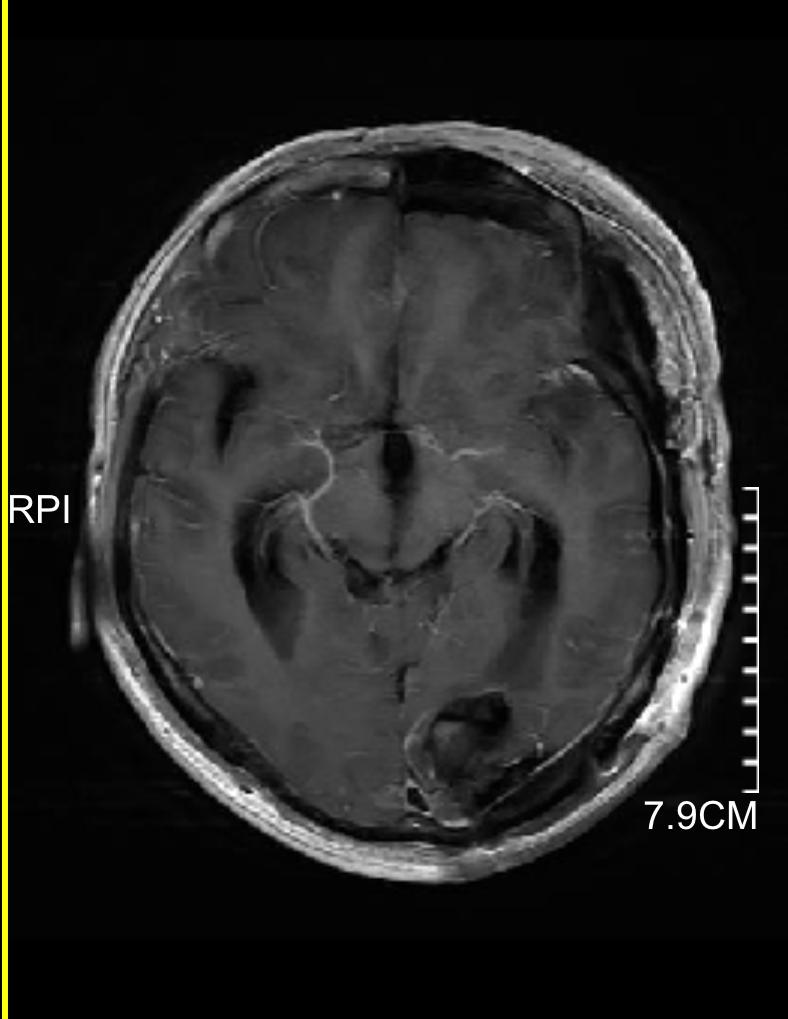

下图的病例是一个以头痛、行走不稳为主要表现,查头颅磁共振发现颅内三个大的转移灶,同时肺部发现巨大肿瘤,脑内病灶给予全部切除,术后根据基因检测结果进行化疗及靶向、免疫治疗。

小脑巨大转移瘤

顶部稍小转移瘤

颞部巨大转移瘤